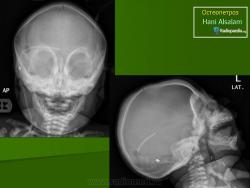

Мраморная болезнь (болезнь Альберс-Шенберга) - семейный генерализованный остеосклероз, протекающий с лейкемической реакцией крови у детей, с анемией и лейкопенией у взрослых, нередко с атрофией зрительных нервов и глухотой. Характерны деформация мозгового и лицевого черепа, заращение придаточных полостей носа плотной бесструктурной костной тканью. Ввиду постепенного сужения отверстий в черепе и межпозвонковых отверстий могут возникать полиморфные проявления поражения периферической нервной системы как на черепном, так и на позвоночном уровнях. В позвонках костные балки губчатого вещества утолщены и уплотнены. В трубчатых костях отмечается сужение, а затем и исчезновение костномозговых полостей, эпифизы булавовидно утолщены и поперечно исчерчены, имеется склонность к патологическим переломам. Наследуется по аутосомно-рецессивному типу и тогда, проявляясь в фенотипе в первые годы жизни, быстро приводит к смерти, или же - по аутосомно-доминантному типу, проявляясь в 20-40-летнем возрасте. Описал болезнь в 1907 г. Н.Е. Albers-Schonberg.